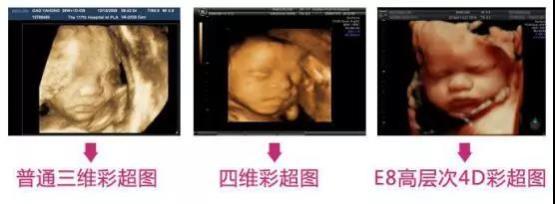

為提高我院診療水平,并更好地為廣大唐山百姓服務(wù),唐山寶島婦兒醫(yī)院在原有美國(guó)GE四維彩超的基礎(chǔ)上,斥巨資引進(jìn)我市目前最先進(jìn)的四維彩超——美國(guó)GE-E8四維彩超。該設(shè)備是目前世界上先進(jìn)的彩色超聲設(shè)備,被譽(yù)為“超聲界的網(wǎng)紅”,是胎兒排畸的尖端設(shè)備。它能夠清晰顯示出未出生寶寶的實(shí)時(shí)動(dòng)態(tài)活動(dòng)圖像和人體內(nèi)臟器官的實(shí)時(shí)活動(dòng)圖像,臨床應(yīng)用于包括腹部、血管、小器官、產(chǎn)科、婦科、泌尿科、新生兒和兒科等多領(lǐng)域檢查。